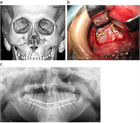

1. 顎顔面外傷は、交通事故、転倒、転落、スポーツ、殴打など種々な原因で生じるもので、 受傷部位により顔面の軟組織損傷(顔面皮膚や口腔粘膜の損傷)、歯および歯周組織損傷(歯の破折、脱臼)、顎顔面骨損傷(上顎骨や下顎骨などの骨折)に大別される。